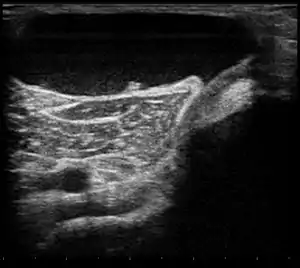

Ultrasound image of Baker's cyst[2]

Diagnosis is by examination. A Baker's cyst is easier to see from behind with the patient standing with knees fully extended. It is most easily palpated (felt) with the knee partially flexed. Diagnosis is confirmed by ultrasonography, although if needed and there is no suspicion of a popliteal artery aneurysm then aspiration of synovial fluid from the cyst may be undertaken with care. An MRI image can reveal presence of a Baker's cyst.